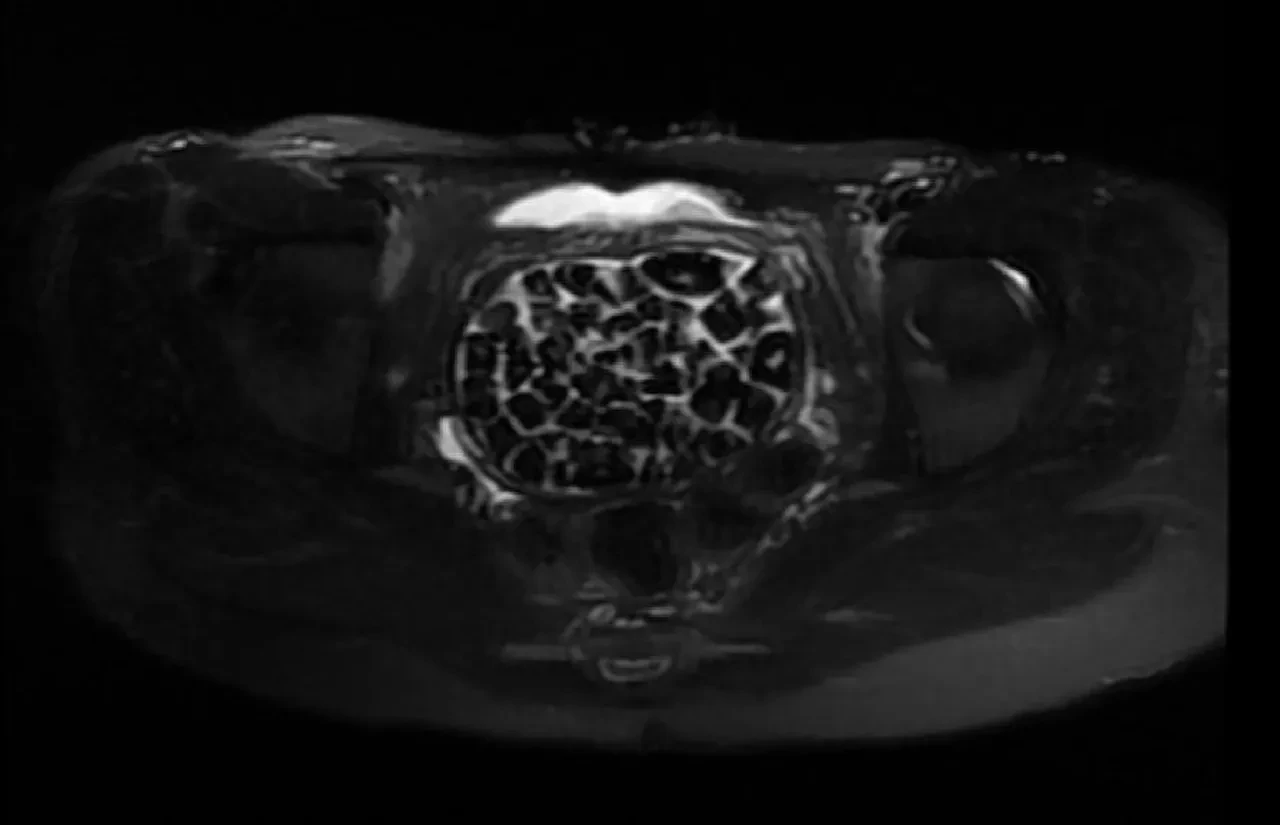

Tedavisi sonrası taburcu edilen genç kız yaşadıklarını anlatırken, operasyonu gerçekleştiren Üroloji Uzmanı Doç. Dr. Erkan Erkan ile Jinekolojik Onkoloji Uzmanı Op. Dr. Emin Erhan Dönmez de nadir olduğunu ifade ettikleri vakaları hakkında bilgi verdi, önemli uyarılarda bulundu. Öte yandan, genç kızın vücudundaki 287 taşın tetkiklerdeki görüntüsü dikkat çekerken taşlar üzerine de incelemeler yapılacak.

Hastasının durumuna yönelik konuşan Üroloji Uzmanı Doç. Dr. Erkan Erkan, "Hastamızın 2004 yılında doğduğunu ardından doğar doğmaz ekstrofi vezika dediğimiz 50 binde bir görülen bir anomaliden dolayı art arda ameliyatlar geçirdiğini öğrendik. 10 yaşında yine bir ameliyat geçirmişti, gerekli görüntüleme ve tetkiklerimizi yaptırdık. Normalde mesanesinin olması gereken yerin hemen arka kısmında taşlarla dolu bir kese olduğunu gördük, bunun üzerine ek görüntülemeler; MR çektirdik. Hastamız çelişkili açıklamalar almıştı, kendi radyolojik kliniğimiz ve edindiğimiz konsültasyonlarda taşların mesanede değil vajinal boşlukta oluştuğunu düşündük, bir planlama yaptık. Kadın doğum hocamızın da çabasıyla taşları tamamen temizledik ardından ileride normal bir hayat sürmesi bakımından oraya plastik cerrahi yaptık. 287 adet taş çıkardık, pratikte gerçekten görünce çok şaşırdık çünkü bu aynı zamanda literatürde çok nadir görülen bir olay. Biz ameliyata hazırlanırken de teorik olarak biraz araştırdık. Literatürde gördüğümüz kadarıyla buna benzer bu tanıma uyan bir vaka vardı. Literatürde sanırım yayınlanmış 2’nci vaka olacak. Farkındalık çok önemli, bilinçli bir hastamız vardı. Doğumsal anomaliyle doğan çocuklarımızda ileride bunlara bağlı bazı sıkıntılar çıkabileceğinin öngörülmesi lazım. İlgili tedavilerini alsalar bile düzenli takiplere gelmeleri gerekiyor. İleride eğer dikkat etmezse ki zannetmiyorum, tekrarlayabilir. Bu rahatsızlık ekstrofi vezikal epispadias durumu çok nadir bir durum" dedi.